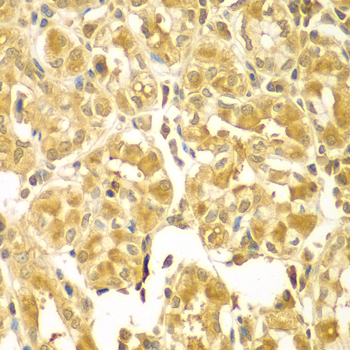

Immunohistochemistry of paraffin-embedded human gastric using SESN2 antibody. |